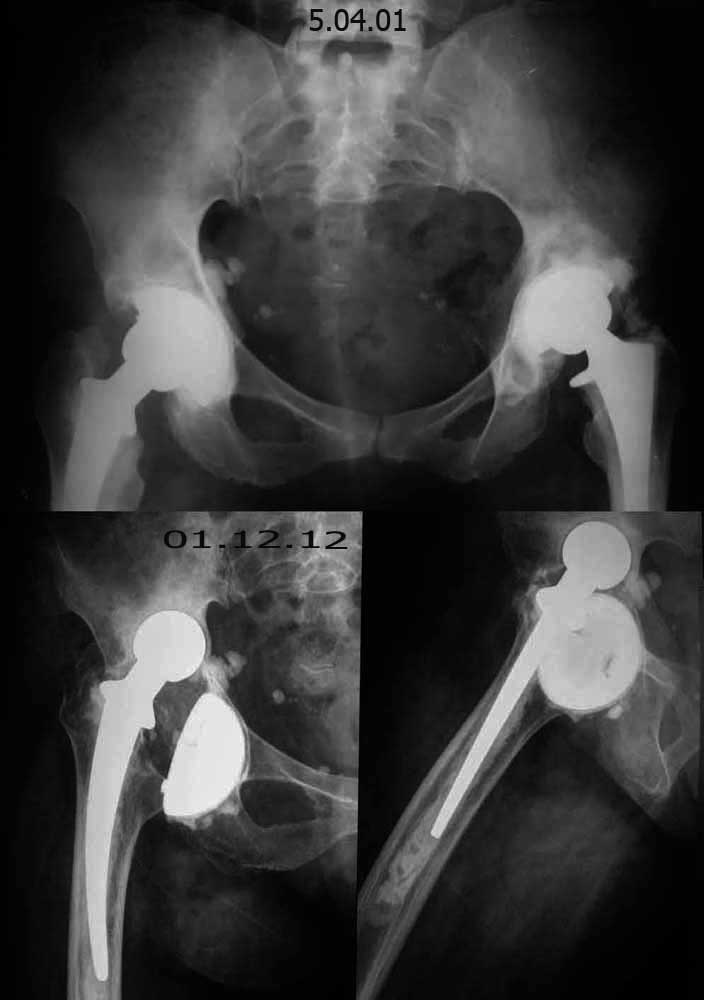

Уважаемые коллеги, помогите определиться  с  тактикой лечения! Больная Л. 56 лет,  20 лет страдает ревматоидным полиартритом.  В 1987 году выполнена операция- артропластика левого тазобедренного сустава по Кулишу. В 1997 году оперирована - тотальное эндопротезирование правого тазобедренного сустава. В 1998 году оперирована - тотальное эндопротезирование левого тазобедренного сустава.  1,5 года назад больная упала, после чего стала отмечать боль в области правого тазобедренного сустава.

Локально: правая нижняя конечность укорочена на 1-1,5см. по сравнению с левой. Движения в правом тазобедренном суставе: сгибание - 35-40º, разгибание-10º, отведение- 15º, приведение-10º, наружная ротация-20-25º, внутренняя ротация-0º.

Движения в левом тазобедренном суставе: сгибание - 75-80º, разгибание-15º, отведение- 30º, приведение-20º, наружная ротация-25-30º, внутренняя ротация-20º.